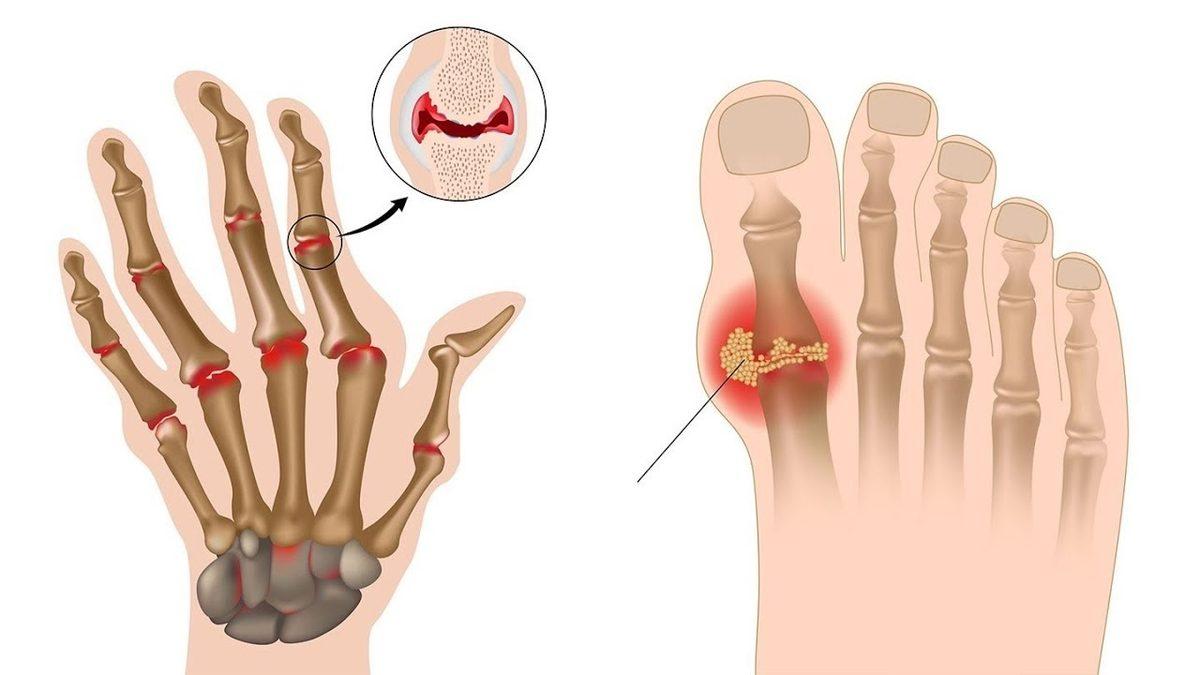

Gut hastalığı en geniş tanımıyla bir eklem iltihabı hastalığıdır. Genel olarak fazla protein alımı sonrası kana karışan ürik asit birikir ve dışarı atılamaz. Dışarı atılmayan ürik asit ayak başparmağı başta olmak üzere diğer ayak eklemlerinde kristalleşerek ağrı ve hassasiyete neden olan bir iltihap oluşturur.

Gut atağının çoğu zaman ilk ortaya çıktığı yer ayak başparmağı eklemidir. Ayak bileği, diz ve ilerleyen zamanlarda omurga sisteminde bile iltihap oluşturabilir. Gut atağı her zaman eklemlerde meydana gelir çünkü ürik asit gece kan sıcaklığı azalınca eklemlerde toplanarak kristalize bir hal alır.